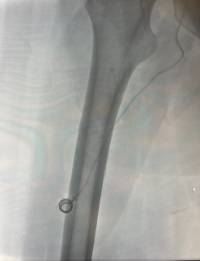

La novedad llega con la incorporación del FICC PORT, un dispositivo similar al PICC PORT, pero que se implanta en el muslo del paciente. Esta ubicación alternativa resulta muy útil en casos en los que las venas de los brazos no pueden utilizarse, ya sea porque están dañadas, agotadas o presentan alguna contraindicación médica.

Gracias a esta técnica, el hospital puede ofrecer una solución segura, cómoda y avanzada a pacientes con necesidades especiales de acceso venoso, mejorando su calidad de vida y evitando procedimientos más invasivos.

Con esta primera implantación de un FICC PORT, el Hospital Universitari General de Catalunya se sitúa entre los pocos centros que disponen de equipos especializados y formados para realizar este tipo de procedimientos, reafirmando su compromiso con la innovación, la excelencia asistencial y el bienestar de sus pacientes.